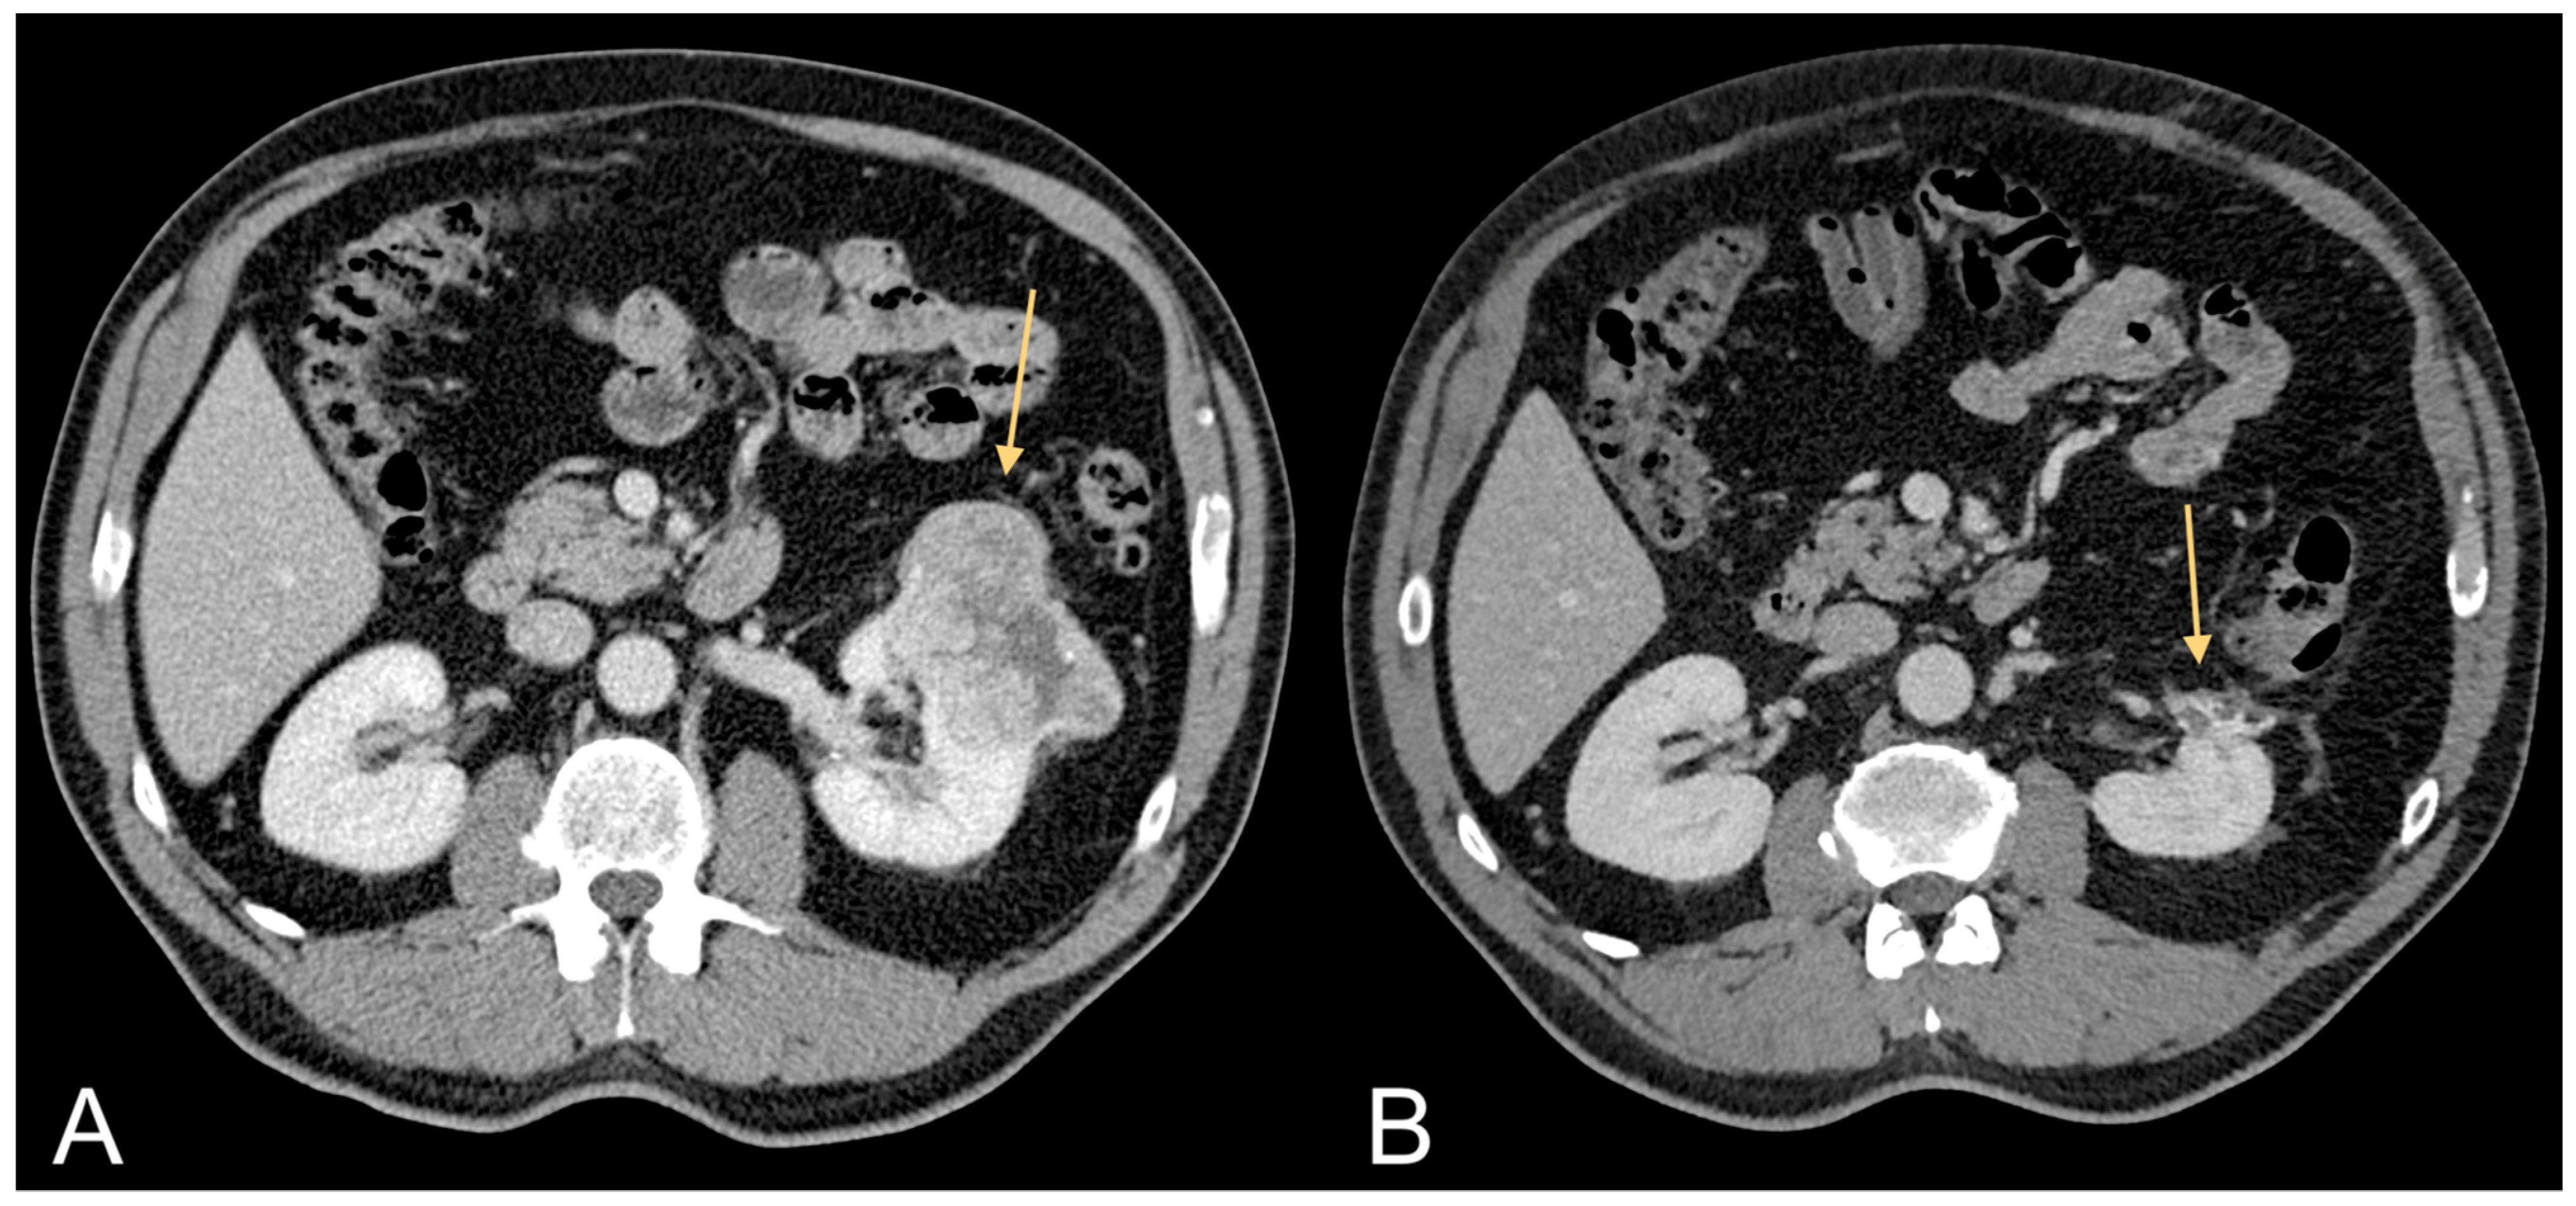

Figure 1.

Contrast-enhanced CT images of a 75-year-old male patient showing CRC (light orange arrow in (A)) and associated excessive amount of VAT (B).